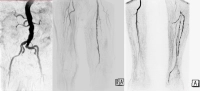

Ejemplo de película

- estenosis subtotales de la A. femoralis superficialis izquierda

- oclusión de la A. poplitea sección I – III

- oclusiones parciales de todas las arterias de la pierna inferior

- oclusión del arco plantar primario y secundario

Estado post bypass venoso femoro-poplíteo derecho, V. saphena magna autóloga consumida, izquierda de calibre demasiado débil → bypass aloplástico.